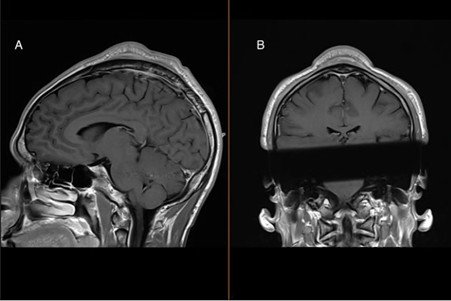

3. Bir Adam, Az Pişmiş Domuz Pastırması Yedikten Sonra Beyninde Bir Solucan Büyüdü

Pastırma severler, başka tarafa bakmanızı tavsiye ederiz! ABD’de orta yaşlı bir adam, migren şikâyetiyle doktora gittiğinde büyük bir şok yaşadı. Genellikle domuzları enfekte eden bir tenya türü olan Taenia solium’un larvalarıyla enfekte olduğunu öğrendi. Larvalar, adamın beyninin içine küçük kesecikler veya kistler halinde yerleşmiş ve kafatasının arka kısmında şişlik ve ağrıya neden olmuştu. Doktorlar, adamın az pişmiş, “yumuşak” domuz pastırması yedikten ve tuvaleti kullandıktan sonra ellerini düzenli olarak yıkamadığı için enfeksiyon kaptığını tahmin ettiler.